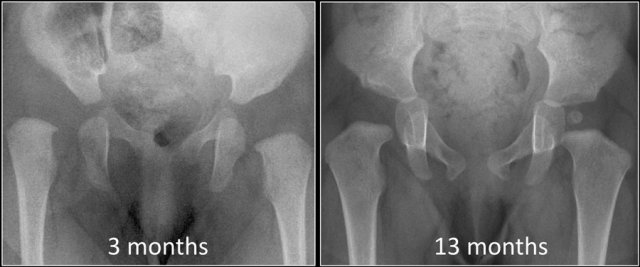

There are children who are born with normal hips who develop dysplasia (figure).

In this case the child had a neuromuscular disorder which caused the hip to become dysplastic and dislocate.

On the other hand there are children who are born with dysplasia of the hip that resolves spontaneously or after relatively simple treatment, e.g. a Pavlik harness (figure).

So we have to realize that DDH is a dynamic disease and it is not always present at birth as suggested by the name congenital hip dysplasia.

Treatment is easier and complications are less likely to occur when DDH is diagnosed early.

In this case at 13 months the only sign of the former dysplasia is the delay of the femoral head to ossify.